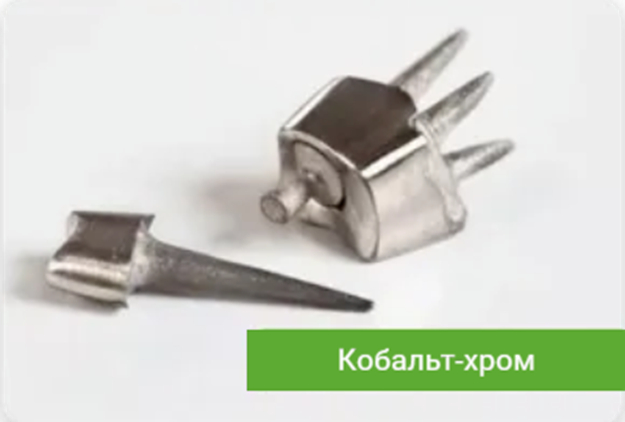

Кобальт-хром считается основным материалом, из него делают 99,9% всех вкладок. Дешевый, пластичный, надежный, неподотчетный, минимум аллергий… короче, твой бро.

Вкладки также бывают однокорневые и многокорневые, разборные и неразборные.

Многокорневая вкладка, как нам подсказывает Капитан Очевидность, фиксируется сразу в несколько корней. Это осуществимо, когда корни идут параллельно, например у верхней четверки. Если говорить про 6 и 7, где корни торчат рогаткой, то в дело вступают вкладки разборные, когда некоторые штифты делаются съемными и устанавливаются в момент фиксации вкладки через её культевую часть. Их философия заключается в том, что они мол лучше держатся в зубе за счет расклинивающего эффекта.